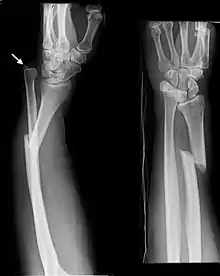

| Galeazzi fracture. Arrow points at the dislocated ulnar head | |

The Galeazzi fracture is a fracture of the distal third of the radius with dislocation of the distal radioulnar joint. It classically involves an isolated fracture of the junction of the distal third and middle third of the radius with associated subluxation or dislocation of the distal radio-ulnar joint; the injury disrupts the forearm axis joint.[1]